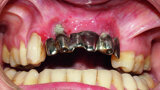

Fig. 1 : Initial prostheses: Lip support was ensured by a large false gingiva, and fractured cosmetic material at the right maxillary canine was evident. The patient’s smile showed the prosthetic teeth placed off-centre and an infiltration at the right lateral incisal level.

Fig. 2 : Initial prostheses: Lip support was ensured by a large false gingiva, and fractured cosmetic material at the right maxillary canine was evident. The patient’s smile showed the prosthetic teeth placed off-centre and an infiltration at the right lateral incisal level.